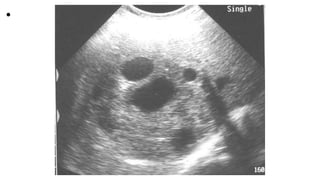

Unilocular cysts are seen

with daughter cysts inside,

they are the hall mark of

hydatid disease.

• Unilocular cysts areseen with daughter cysts inside, they are the hall mark of hydatid disease.